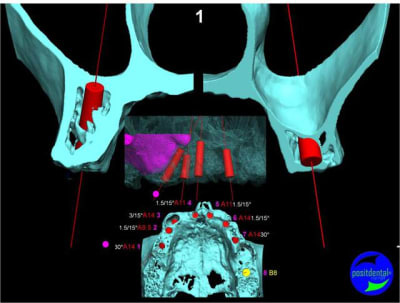

Projet implantaire:

Extraction, pose d’implants Ankylos, pose des piliers Standard définitifs, mise en charge immédiate bi-maxillaire en une chirurgie.

Maxillaire supérieur – extraction 13, 26, 7 implants en MCI, 1 implant en MCR pose summeurs, densification par ostéotme, comblement osseux, bridge provisoire sans fausse gencive avec renfort métallique.

3D

en attendant la pano voici les coupes de la S.I.A.O.